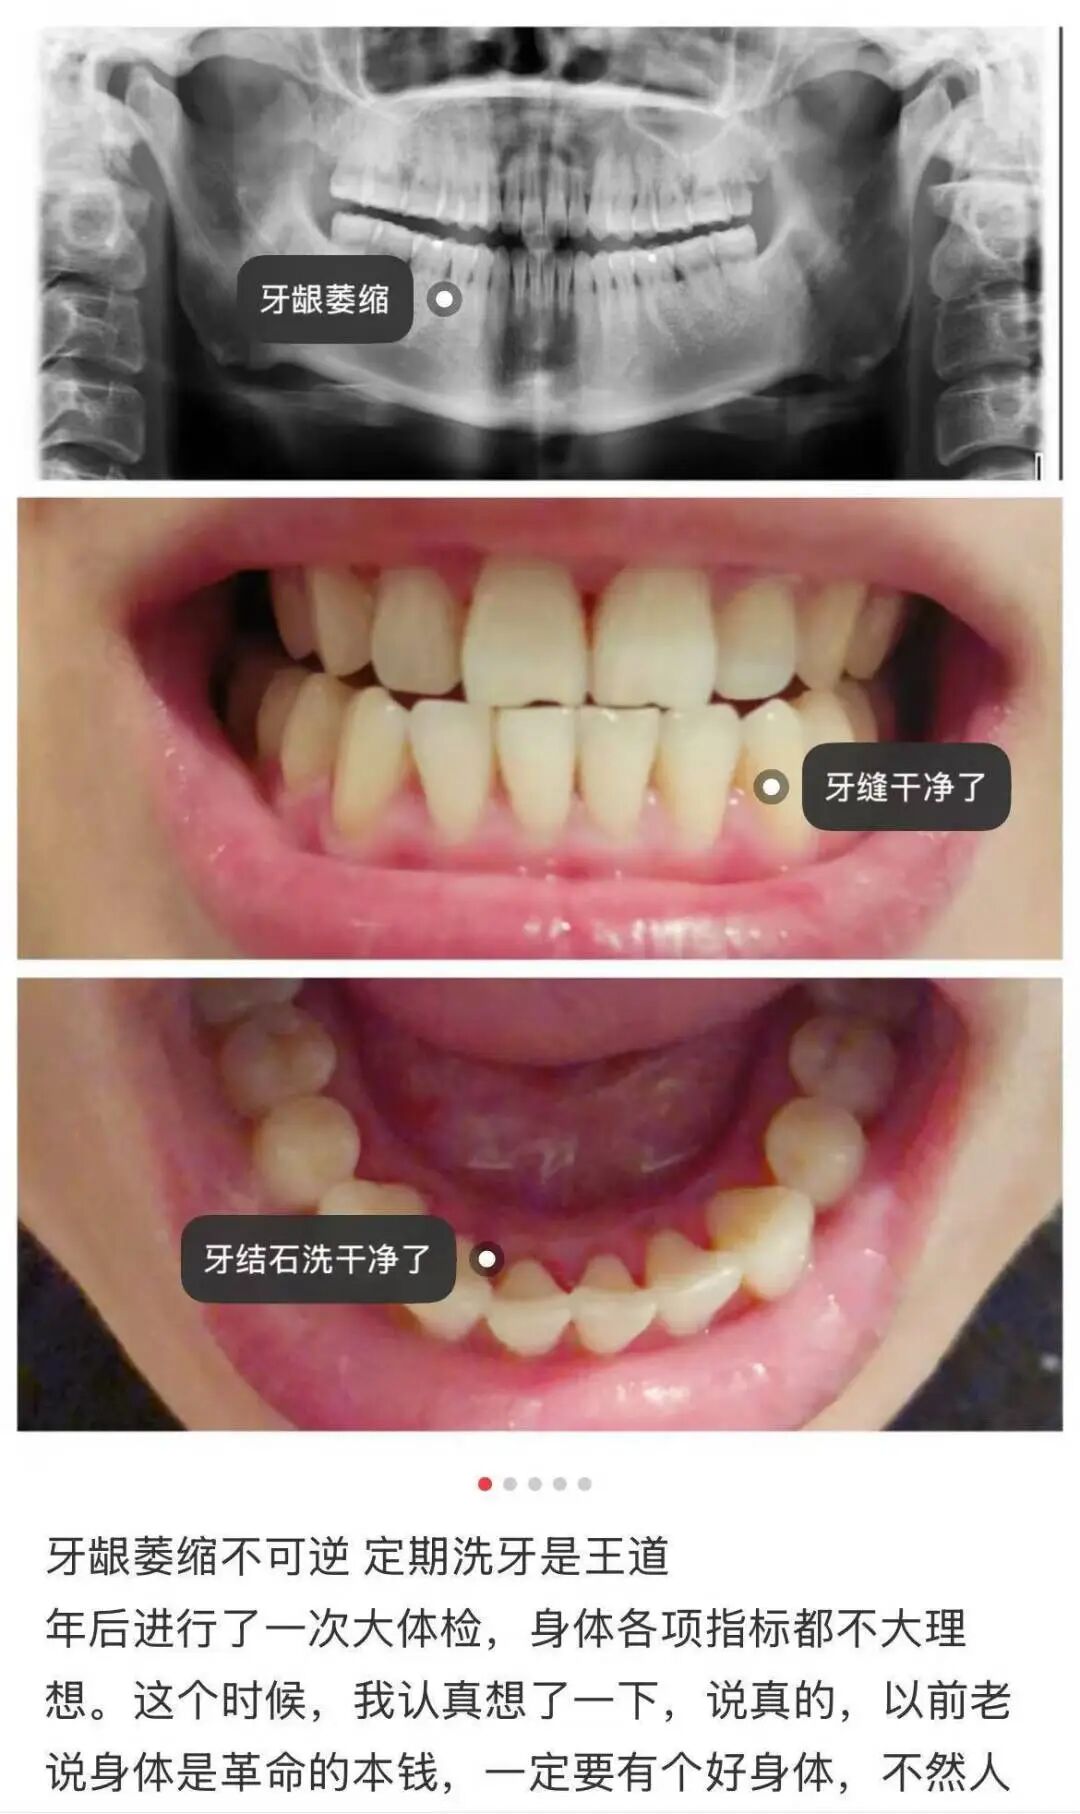

一般来说,最有效的防止它恶化的方式,就是定期洗牙!

图片来源:小🍠

现在市面上尤其流行一种牙膏,宣称能「恢复牙龈」——如果不是钱多得没处花,不必买!

好好刷牙是有助于保护牙龈,但已经萎缩的牙龈是不可逆的,不会因为用了特别产品就长回来。